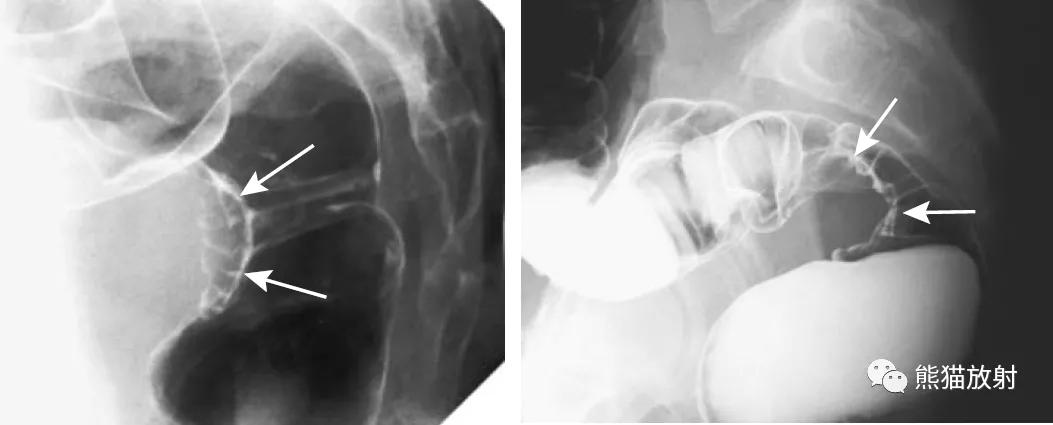

乙状结肠扭转。消化道造影侧视图可见乙状结肠局部走行扭曲(箭头)。

巨大的乙状结肠憩室。X线平片示盆腔巨大充气结构(箭头)。钡灌肠确定为憩室(箭头),并与结肠相连。